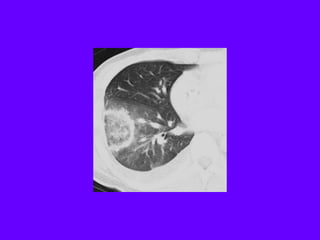

A 27-year-old man is referred to you for evaluation of an

abnormal chest radiograph. About 5 months ago, he consulted

a doctor because of excessive thirst. Evaluation resulted in the

diagnosis of diabetes insipidus, which responded favorably to

desmopressin administered nasally. Recently, he started to

notice shortness of breath when climbing stairs, and a chest

radiograph was obtained.

•Patient history reveals significant tobacco smoking, up to two

packs daily, for at least 14 years. The patient noticed the

shortness of breath for at least 2 years, and recently, he noted

a point of tenderness over the chest wall, lateral to the

posterior axillary line on the left.

•Oxygen saturation is 94% while breathing room air, and the

rest of his vital signs were normal. Auscultation reveals only

rare crackles without prolongation of the expiratory phase.

There is a point of tenderness over the left sixth and seventh

ribs in the posterior axillary line, and a chest CT scan is

obtained.